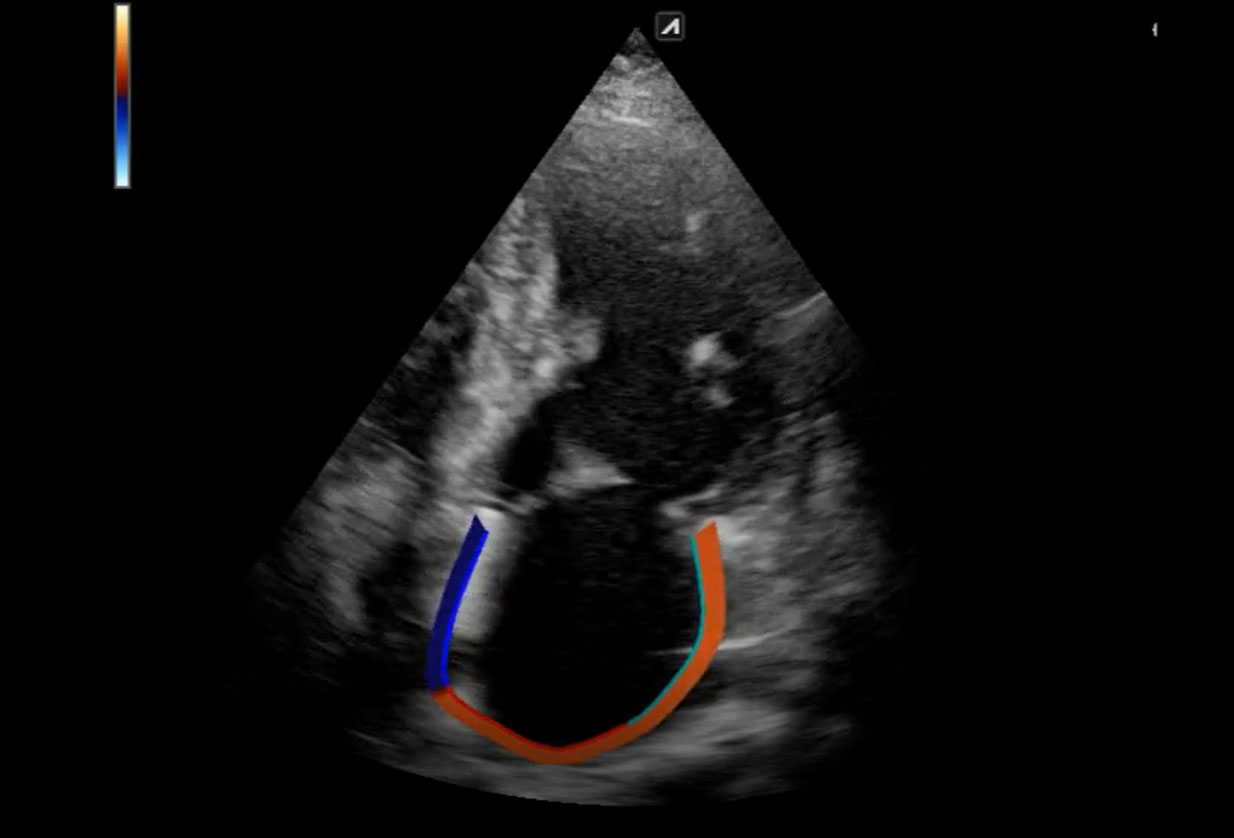

Μελέτη ιστικής παραμόρφωσης (myocardial strain)

Στο ιατρείο μας έχουμε τη δυνατόητα εφαρμογής νεότερης τεχνολογίας υπερηχογραφικών τεχνικών (longitudinal strain) που αυξάνουν κατά πολύ την διαγνωστική αποτελεσματικότητα. Το λογισμικό αναλύει την λειτουργία της καρδιάς και εντοπίζει τμηματική και συνολική δυσλειτουργία που δεν ειναι εμφανής στο γυμνό μάτι.

Εξειδικευμένη εξέταση μελέτης ιστικής παραμόρφωσης

H εξέταση γίνεται με εφαρμογή νεότερης τεχνολογίας υπερηχογραφικών τεχνικών (longitudinal strain) που αυξάνουν κατά πολύ την διαγνωστική αποτελεσματικότητα.